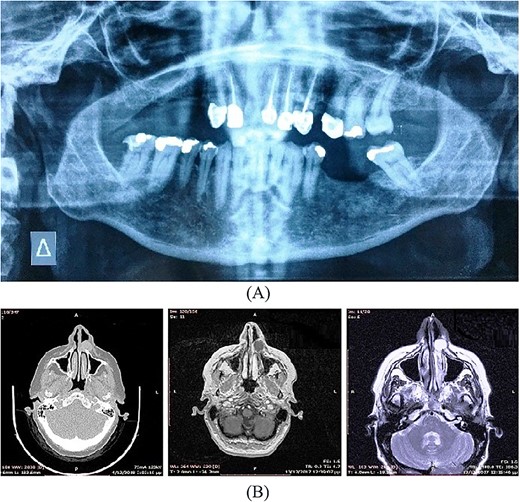

A 57-year-old-Caucasian female patient was referred to our department, complaining of swelling of the left anterior maxillary area (Fig. 5a). The patient had been aware of the swelling for 20 months, but without any pain or tenderness. Physical examination revealed a 2-cm soft lump with normal overlying mucosa and mobile over the lesion (Fig. 5b). An extraoral asymmetry over the left nasolabial sulcus and obstruction of the left nostril was observed. The teeth, adjacent to the lesion, were endodontically treated. The cyst was not identified on the panoramic radiograph of the jaws (Fig. 6a). CT and magnetic resonance imaging (MRI) images showed an oval lesion with slight peripheral enhancement emanating from the lateral wall of the left nasal cavity (Fig. 6b). The lesion, measured 1.7 × 1.9 × 1.3 cm, was considered a simple cystic lesion. No erosion was evident on the underlying maxillary bone, despite its extension anteriorly to it.